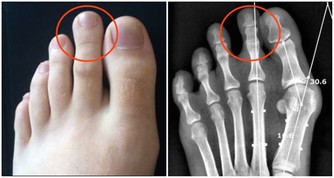

4、還有一种血液粘稠比較嚴重的現象,體現在指甲上,有些人指甲本身長得就有點往裡凹,但是指甲內陷嚴重的話,那種線形凹陷就是與血管有關了,血液粘稠了就會影響血液循環了。